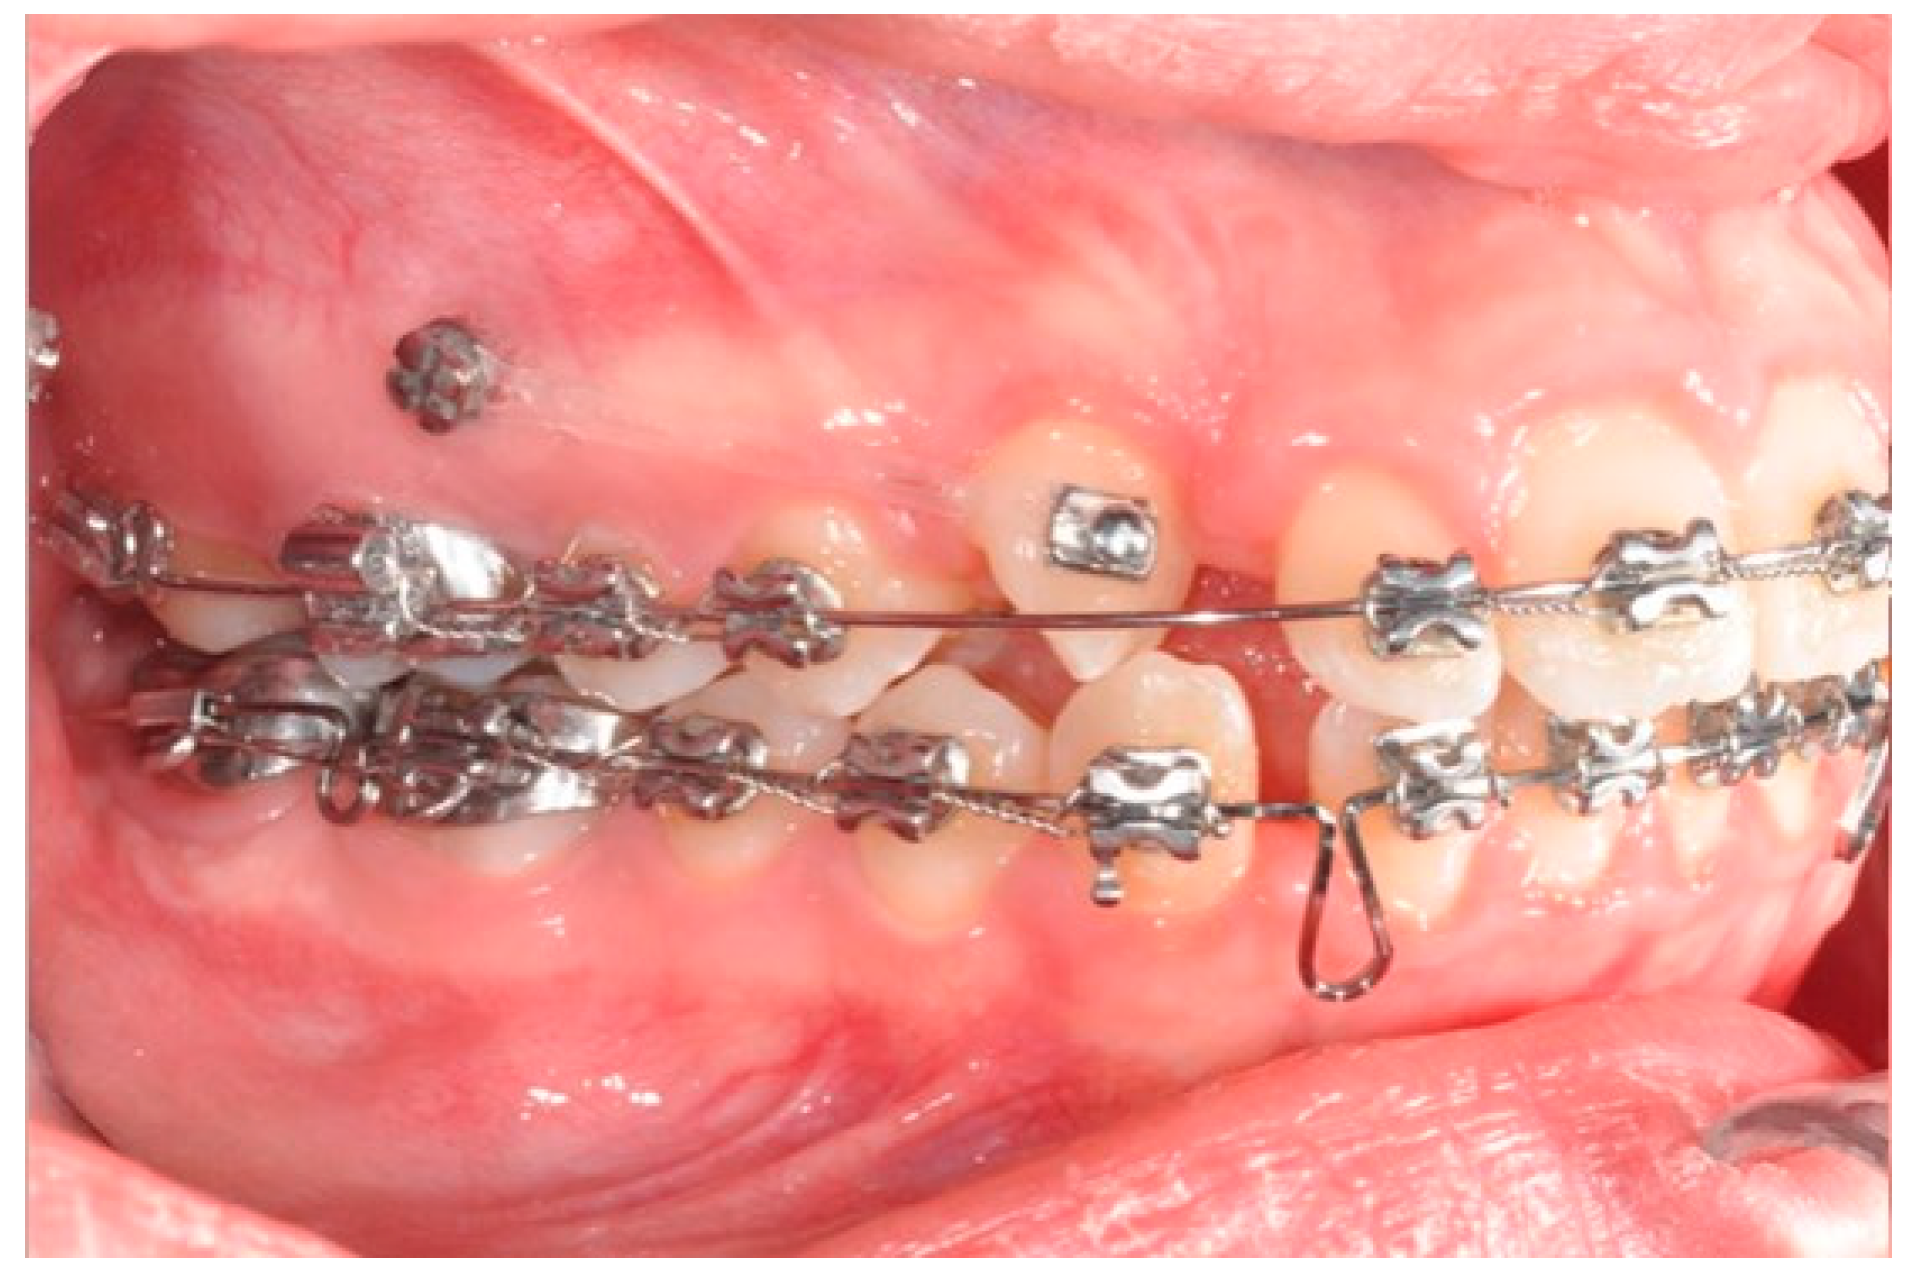

A 12-year-old girl with the second skeletal class (ANB 5), a high angle (FMA 27), and a facial index of 0.67 was selected. Soft tissue analysis showed a convex profile with a Z angle equal to 57 and an FMIA angle close to 55. The IMPA angle was 98. The analysis of the dental cast revealed a spee curve of 3.5 mm (Table 1). The occlusion presented a first molar class to the left, and a light second class to the right with 1 mm crowding in the lower jaw. The overjet was 0. The upper canines were impacted (Figure 1, Figure 2 and Figure 3). The patient’s chief complaint was altered aesthetic perception due to reduced dimensions of the deciduous canines. The treatment objectives were to retrieve space for upper canines’ eruption, level the spee curve, upright the lower incisors, and reduce the impact of the convex profile through occlusal vertical control to facilitate counterclockwise mandibular rotation.

Figure 1. Initial intraoral photos.